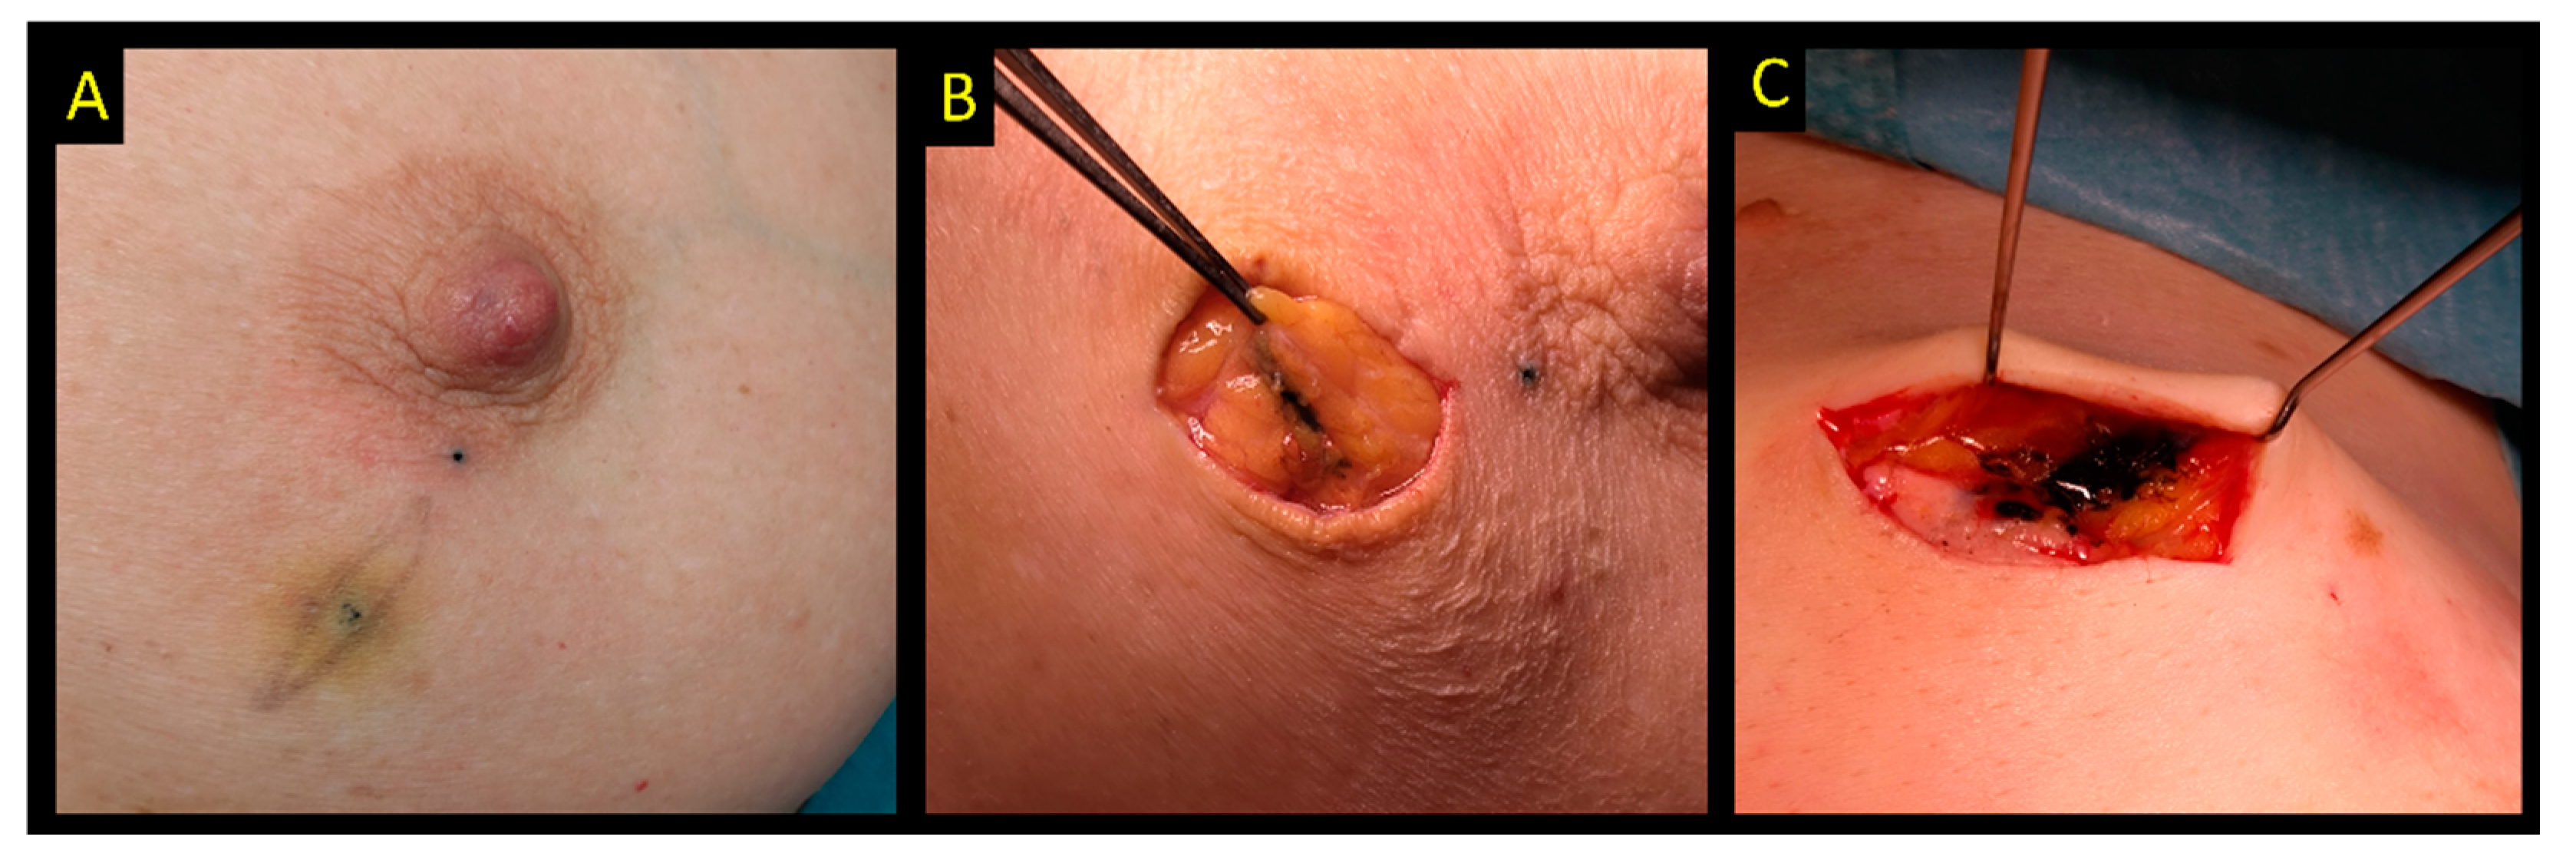

2.8. Carbon Suspension

- Canavese, G.; Catturich, A.; Vecchio, C.; Tomei, D.; Estienne, M.; Moresco, L.; Imperiale, A.; Parodi, G.C.; Massa, T.; Badellino, F. Pre-operative localization of non-palpable lesions in breast cancer by charcoal suspension. Eur. J. Surg. Oncol. 1995, 21, 47–49. [Google Scholar] [CrossRef]

- Ko, K.; Han, B.K.; Jang, K.M.; Choe, Y.H.; Shin, J.H.; Yang, J.H.; Nam, S.J. The value of ultrasound-guided tattooing localization of nonpalpable breast lesions. Korean J. Radiol. 2007, 8, 295–301. [Google Scholar] [CrossRef]

- Mathieu, M.C.; Bonhomme-Faivre, L.; Rouzier, R.; Seiller, M.; Barreau-Pouhaer, L.; Travagli, J.P. Tattooing breast cancers treated with neoadjuvant chemotherapy. Ann. Surg. Oncol. 2007, 14, 2233–2238. [Google Scholar] [CrossRef]